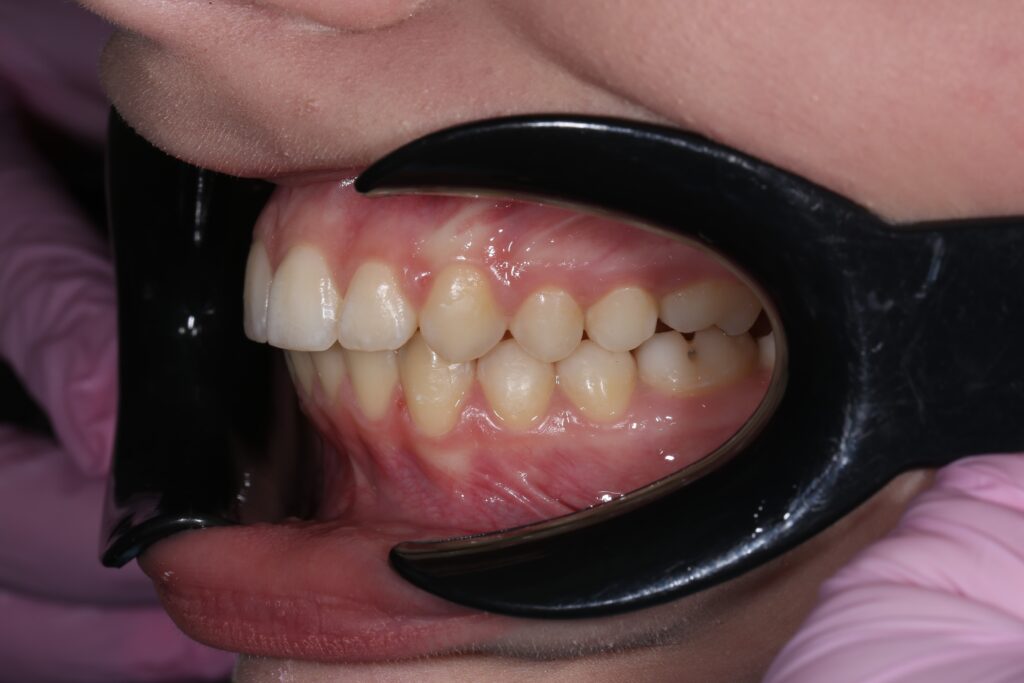

Результаты

результат лечения брекет-системой